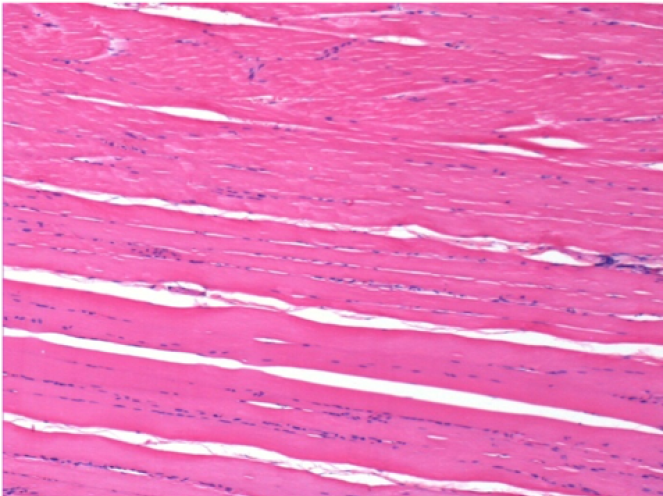

7 months after Endopeel Injection

7 months (D210)after Endopeel IM Injection 0.1ml in the right pretibial muscle.

Complete Restitutio ad integrum after 7 months

L : Control-100xD210

R:100xD210

L :Control 50xD210

R50X-D210